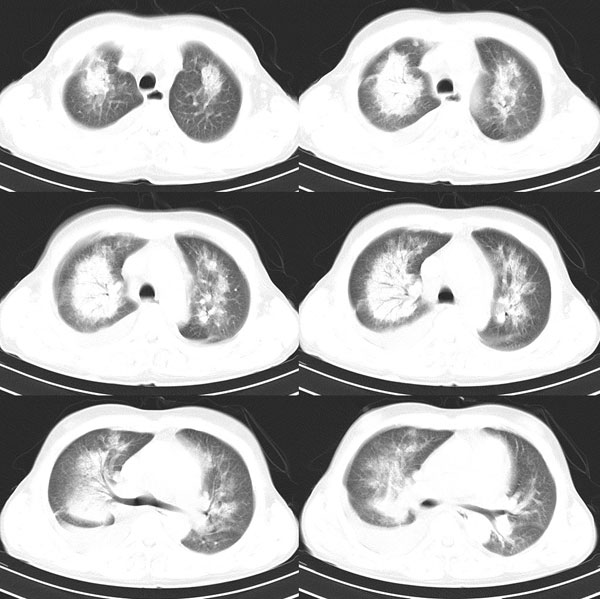

以下是引用wxy7406在2006-11-9 20:45:00的发言:[br]这个人是个男性患者,双侧乳腺明显呈块状,不像就是好东西;双侧肺上叶均见云絮状致密灶,内可见支气管影,右侧肺门去见肿大淋巴结,右侧胸腔见条片状积液。[br]考虑支气管肺泡癌。

以下是引用lkc8963在2006-11-10 0:29:00的发言:[br]大心脏+对称性大片影+双侧胸液,考虑心源性肺泡性肺水肿。请结合临床考虑是何种心脏病。